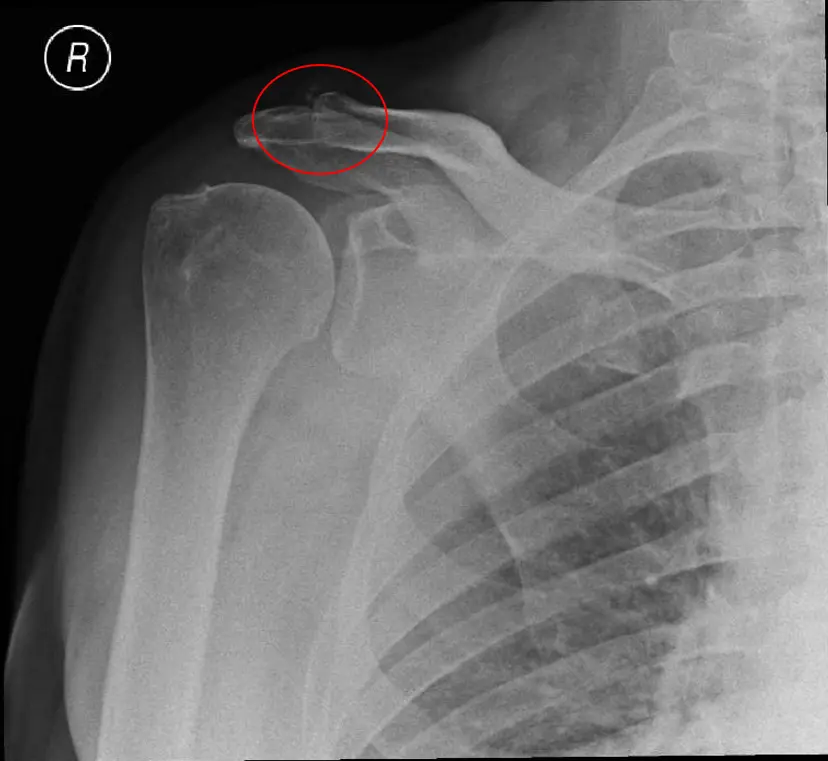

Αρθρίτιδα Ακρωμιοκλειδικής Άρθρωσης

Είναι η εκφύλιση των αρθρικών επιφανειών της κλείδας και του ακρωμίου. Αυτή μπορεί να προκληθεί είτε λόγω χρόνιας καταπόνησης είτε ύστερα από ένα τραυματισμό ή εξάρθρημα αυτής. Ωστόσο, στη μεγάλη πλειοψηφία των περιπτώσεων δεν δύναται να εξακριβωθεί η ακριβής αιτία της νόσου. Η αρθρίτιδα της ακρωμιοκλειδικής έχει συχνά ως απόρροια την στένωση του υποκείμενου υπακρωμιακού χώρου και συνεπώς της την εμφάνιση του συνδρόμου υπακρωμιακής προστριβής

Διάγνωση

Ο ασθενής με αρθρίτιδα της ακρωμιοκλειδικής χρειάζεται εκτίμηση από εξειδικευμένο Ορθοπαιδικό Χειρουργό. Ο κ. Βλάχος αφού λάβει το ιστορικό σας και σας εξετάσει πολύ προσεκτικά, θα πραγματοποιήσει υπερηχογράφημα με σκοπό να ελέγξει την ακεραιότητα των τενόντων του στροφικού πετάλου. Επίσης θα χρειαστεί η λήψη μιας ακτινογραφίας ώστε να αποκλειστεί το ενδεχόμενο γενικευμένης οστεοαρθρίτιδας ή άλλων παθήσεων του ώμου. Σε συγκεκριμένες περιπτώσεις ο ιατρός θα χρειαστεί να σας παραπέμψει για μαγνητική τομογραφία του ώμου.